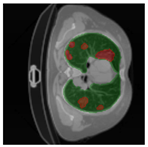

In Table 6, a comparison of the ground truth and prediction results of each model is presented in 2D, along with the 3D projection of each model. The visual analysis of the predictions provides additional insights into the performance of each model. The visualizations demonstrate that Attention UNet captures the intricate details of the lung construction more accurately, resulting in more precise segmentation of the infected areas compared to other models.

Table 6.

Comparison of ground truth and model prediction results using UNet, LinkNet, Attention UNet, UNet 3+, and TransUNet.